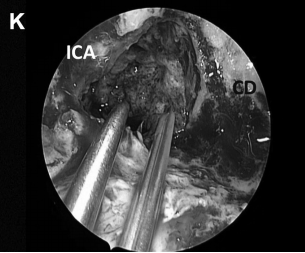

▼(K)使用 TachoSil、纤维蛋白胶封闭颅腔